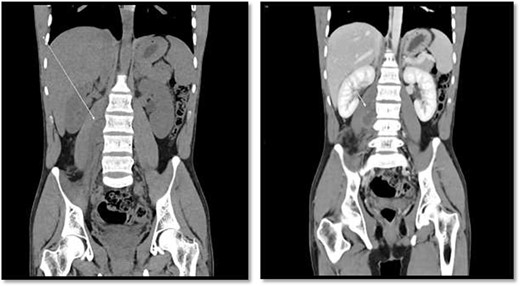

CT scan showed there is 4 × 3 cm lobulated mass noted at the right paravertebral space invading the right psoas muscle at the level of L3 and L4 and extending through the neural foramina, the associated with epidural component compressing the spinal cord from the level of the L2–L4.

An 18-year-old healthy man presented to the emergency department (ED) with 1-day history of right testicular pain and vomiting with no fever nor abdominal pain. Physical examination showed mild tenderness in the right testis, no swelling, normal longitudinal position and cremasteric reflex. Scrotal Doppler ultrasound was performed and showed reduced vascularity in the right testis and the left testis was normal. Moreover, the size and echogenicity were maintained for both testes (Fig. 1). Two months prior to this presentation, the patient presented with the same attack with only mild tenderness in the right testis, and all investigations were within normal limits and he was discharged with oral analgesic drugs. The decision was made to undergo surgical exploration for possible torsion/detorsion of the right testis. The patient was transferred immediately to the operating room for bilateral orchiopexy. The right spermatic cord was engorged with no evidence of ischemia identified and bilateral orchiopexy was done successfully. After the surgery, the patient was kept for observation for 24 h and then discharged. After 2 days from the surgery, the patient came back to ED with testicular pain and post-surgical swelling. We decided to do computerized tomography (CT) scan of the abdominal and pelvis to rule out retroperitoneal pathologies or referred pain. The CT showed 4 × 3 cm lobulated mass noted at right paravertebral space invading the right psoas muscle at the level of L3 and L4 (Fig. 2). The CT scan also showed there is an associated fistula tract between the mass and infrarenal inferior vena cava with thrombosis associated with epidural component extending through the neural foramina compressing the spinal cord from the level of the L2–L4 (Fig. 3). The patient was referred to spinal surgery and CT-guided paraspinal lumbar biopsy was taken. The histopathology came with the diagnosis of Ewing sarcoma. The decision was made by the medical oncology to start on a systemic chemotherapy (vincristine + Adriamycin + cyclophosphamide alternating with ifosfamide + etoposide (VAC/IE)) regimen. After six cycles, the follow-up magnetic resonance imaging demonstrated significant resolution of the right psoas and posterior paraspinal metastatic disease. In addition, further resolution with residual intraspinal extradural metastatic disease noted at right L2–3 and L3–4 levels. The patient is still followed up as an outpatient clinic with medical oncology.

On the left image, there is associated fistulas tract between the mass and infrarenal inferior vena cava with a small hyperdense component may represent hemorrhage or solid component. The right image CT scan showed the mass extending through the neural foramina compressing the spinal cord from the level of the L2–L4.